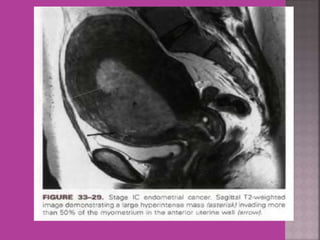

2.Endometrial cancer –Myometrial

invasion, downward extension to cervix.

 Gynaecological cancers--- 1. Cervical cancer –extent of parametrium and pelvic organs , pelvic L.N., Endocervical. 2.Endometrial cancer –Myometrial invasion, downward extension to cervix. 3. ovarian cancer—malignant versus benign mass, ascites , retroperitoneal node > 1cm , Bowel bladder , ano rectal . Parietal peritoneum , liver and or omental metastasis. 4. Pregnancy --- complicated by genital cancers